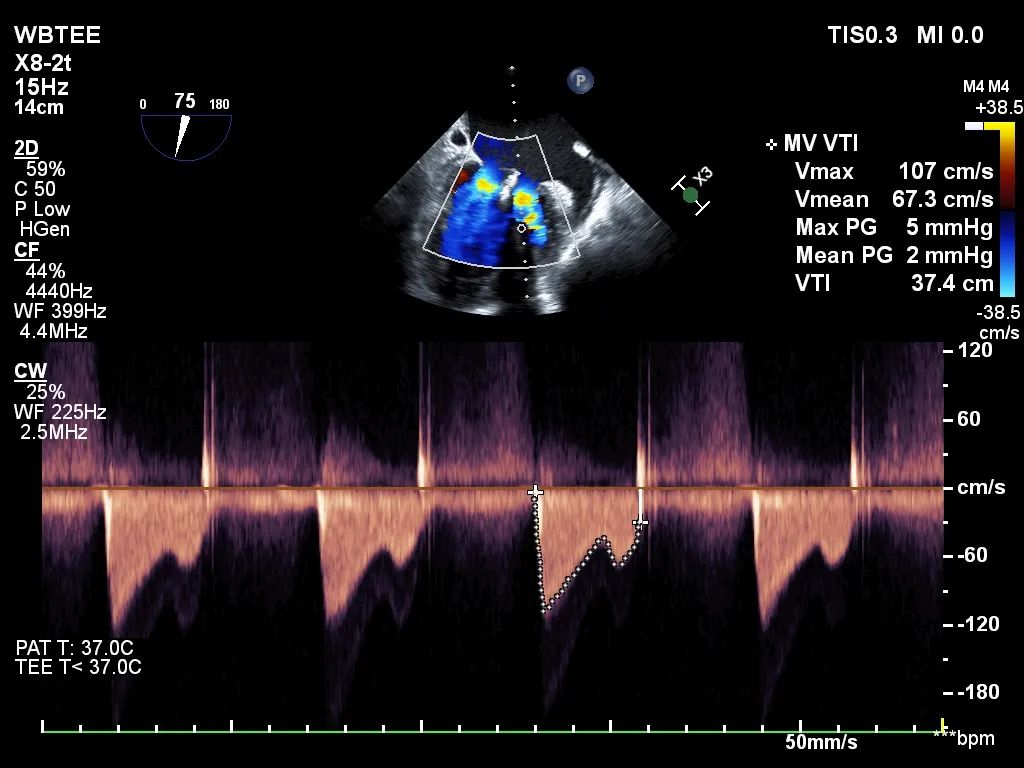

反复测试二尖瓣钳夹的稳定性,超声复查提示二尖瓣夹内侧反流有效改善,外侧仍有部分反流,平均跨瓣压差2mmHg,肺静脉收缩期逆流频谱恢复正向,傅国胜教授团队与超声影像团队充分沟通讨论,计划在二尖瓣夹外侧再置入第二枚二尖瓣夹,遂精准释放第一个二尖瓣夹。

再次反复测试第二枚二尖瓣钳夹的稳定性,超声复查提示二尖瓣反流明显改善,平均跨瓣压差4mmHg。